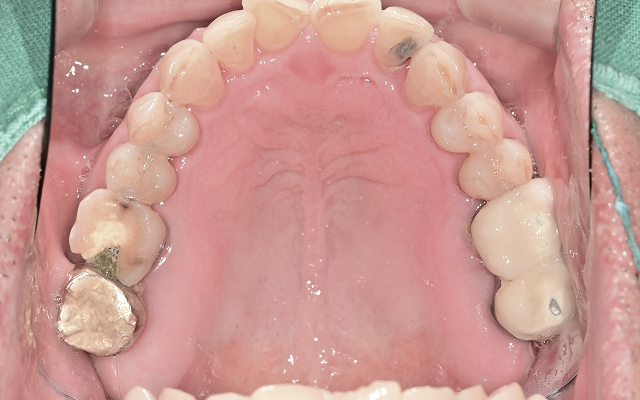

진료 전 구강 스캔과 구내 촬영을 통해

치아 상태를 꼼꼼하게 분석하고 설명드립니다.

엑스레이, 구강 사진, CT 등을 통해 꼼꼼히 진단하고 촬영한 사진을 함께 보며 쉽게 이해하실 수 있도록 설명드립니다.